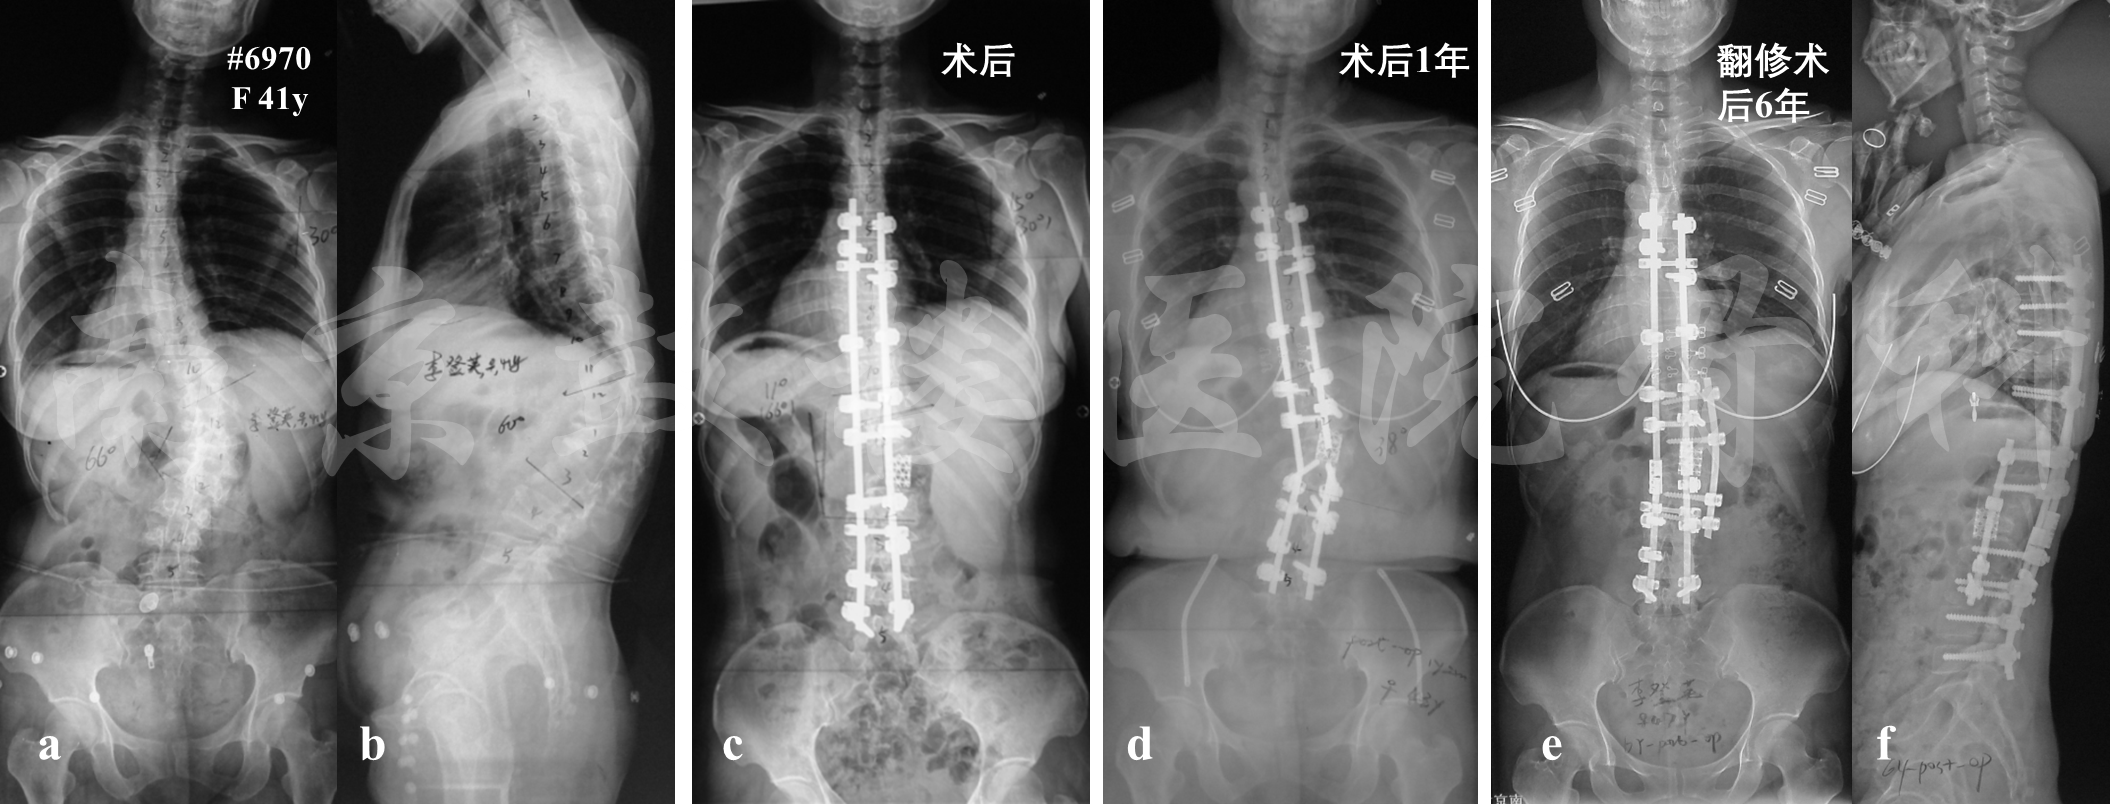

成人脊柱畸形三柱截骨术后断棒发生率高达7.1~15.8%。内固定棒的断裂多发生于术后2年内,断裂水平多与截骨水平一致,其危险因素包括残留后凸畸形、前柱缺损、单棒内固定、外伤、钛网移位等(图3)。

图3 女,41岁,术前X片示侧凸及后凸顶椎均为L1(a, b),因此行L1 PSO截骨术, 前路钛网支撑融合(c),术后1年截骨区假关节形成,出现双棒断裂,钛网倾斜(d),遂行前后路联合翻修术,翻修术后6年无内固定失败(e, f)